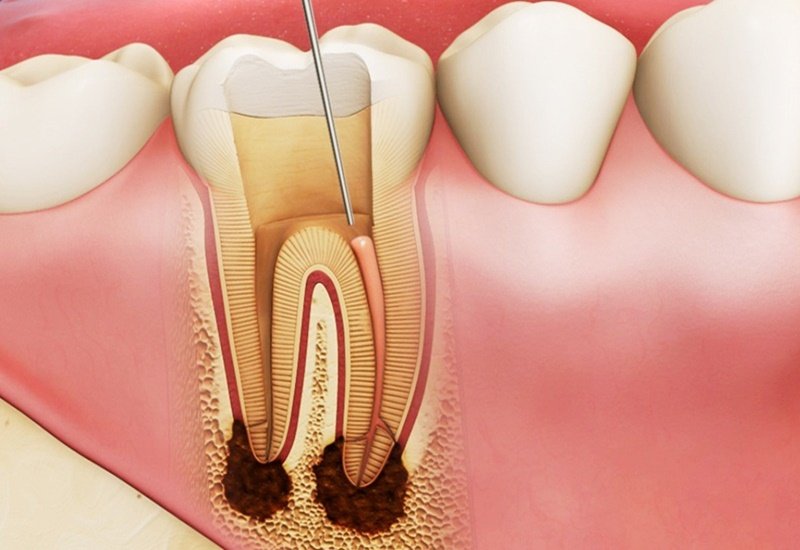

Trước hết, bạn cần hiểu về tủy răng. Tủy răng nằm ở hốc giữa ngà răng và bao gồm nhiều tổ chức khác nhau như mạch máu, thần kinh,… Tình trạng viêm ở tủy và các mô quanh chân răng được gọi là viêm tủy răng. Đây là phản ứng của tủy để chống lại những tác nhân gây bệnh.

- Trường hợp trên răng đã xuất hiện những lỗ sâu lớn, những vết gãy và vi khuẩn xâm nhập và gây viêm tủy, người bệnh sẽ cảm thấy đau buốt, thậm chí có sử dụng thuốc giảm đau mà không thấy đỡ. Khi nhai hoặc tiếp xúc với đồ ăn nóng hay lạnh thì cơn đau càng nghiêm trọng. Với những trường hợp này, các bác sĩ sẽ thực hiện điều trị tủy cho người bệnh. Khi được loại bỏ phần tủy có chứa nhiều vi khuẩn, những cơn đau sẽ dần thuyên giảm.

Nếu không kịp thời điều trị, bệnh sẽ tiến triển thành những ổ viêm ở chân răng và khiến cho việc điều tị tủy răng sẽ khó khăn hơn rất nhiều. Đồng thời, bệnh nhân có nguy cơ phải đối mặt với một số biến chứng nguy hiểm khác như chết tủy, thối tủy, viêm hạch, xương hàm và thậm chí là mất răng,...